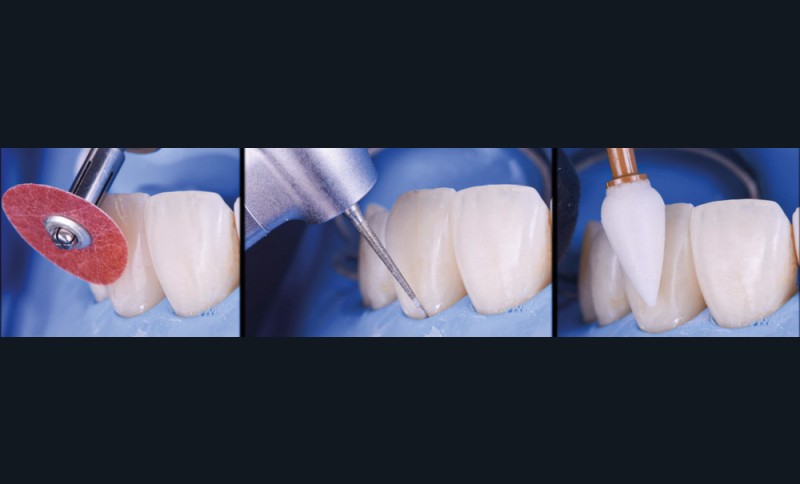

La fermeture des triangles noirs en technique directe avec des résines composites offre une alternative très favorable avec une approche non invasive, esthétique, un coût réduit et une possibilité de réintervention aisée. Plusieurs méthodes ont été proposées : réalisation à main levée sans matrice (à proscrire), avec bande de matrice transparente plate ou galbée, avec matrice postérieure customisée et utilisée verticalement… Il faut bien comprendre qu’aucun coin en bois ou plastique ne pourra être employé pour stabiliser cette matrice, car il empêcherait la création d’un profil d’émergence anatomique convexe en induisant une déformation concave de la matrice à sa base.